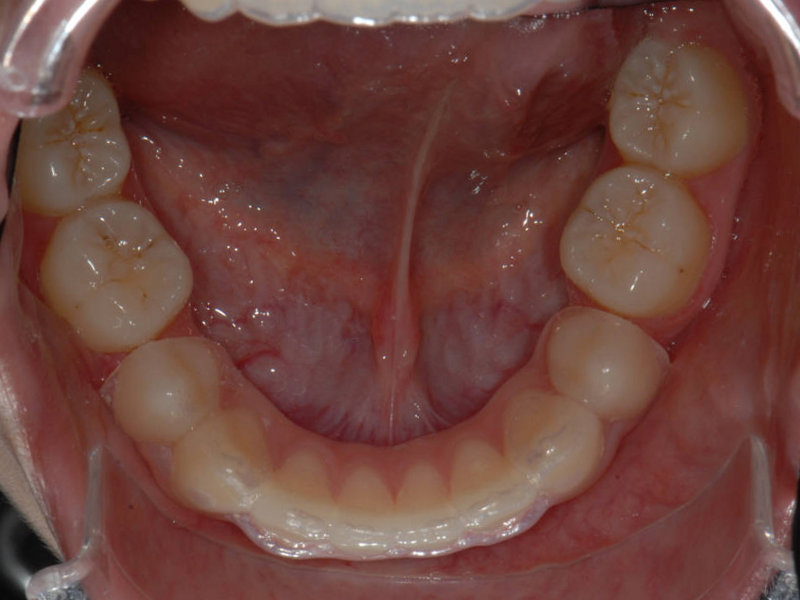

Alexanderplåt